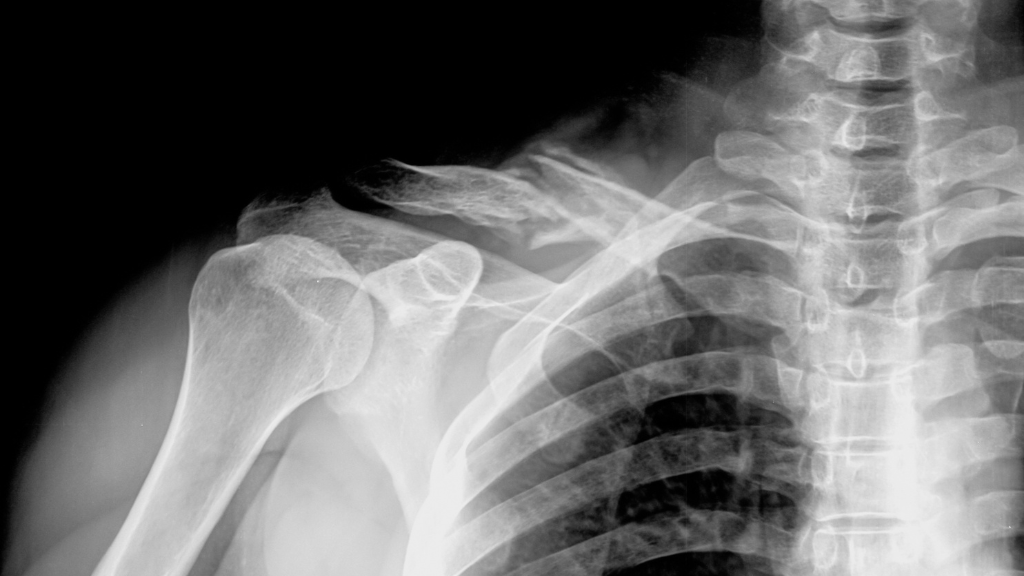

Le calcium est crucial pour maintenir des os robustes. Une consommation excessive de phosphore, sans un apport suffisant en calcium, peut entraîner une déminéralisation. Sur le long terme, cela augmente le risque d’ostéoporose et de fractures osseuses, particulièrement chez les personnes qui consomment des sodas quotidiennement.

Notre corps a besoin d’un équilibre délicat entre calcium et phosphore. Lorsque cet équilibre est rompu, il extrait le calcium des os pour maintenir la stabilité. Cela peut paraître bénin, mais ce processus affaiblit vos os avec le temps. De surcroît, les sodas ne contiennent pas de nutriments essentiels comme vitamines ou minéraux qui favorisent la santé osseuse.

Des recherches ont révélé que ceux qui consomment de grandes quantités de sodas ont des os plus fragiles que ceux qui n’en consomment pas. Les femmes sont particulièrement vulnérables à l’ostéoporose en raison de leur consommation de colas. Il a été prouvé qu’une consommation régulière de sodas augmente les chances de problèmes osseux à l’avenir.